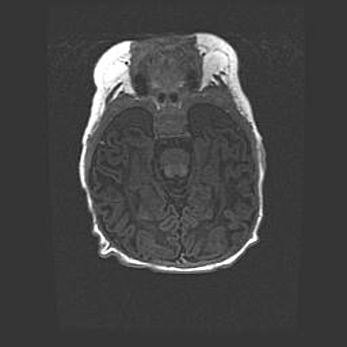

Церебральная ишемия II.

Возраст: 5 дней

Вес: 3400 г

Пол: женский

Окружность головы: 35 см

Срок гестации: 39 недель

Церебральная ишемия – это заболевание, характеризующееся недостаточностью (гипоксией) либо полным прекращением (аноксией) снабжения мозга кислородом по причине закупорки одного или нескольких сосудов. Это приводит к  что метаболическим расстройствам различной степени тяжести в тканях головного мозга, развитию коагуляционных некрозов и гибели нейронов.